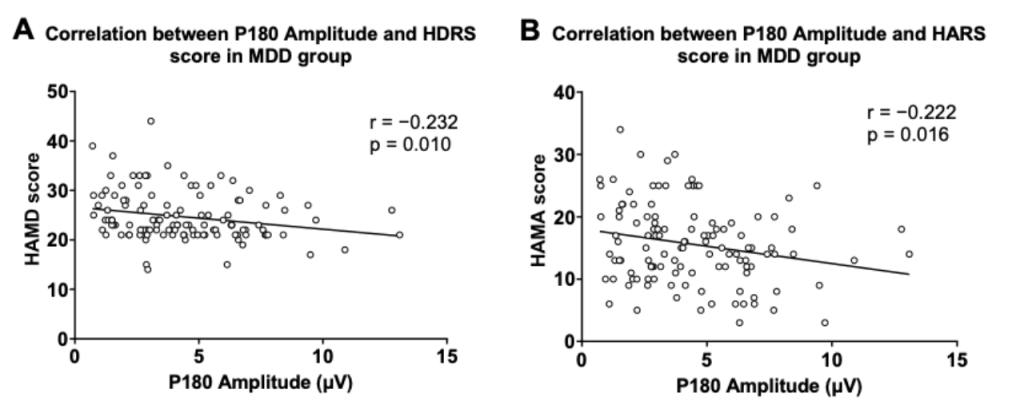

圖2. P180波幅與抑郁及焦慮癥狀得分的關系

圖1分別顯示了健康對照組與患者組的TMS誘發腦電的蝴蝶圖。研究結果顯示,抑郁癥患者P180波幅顯著低于健康對照人群。在抑郁癥患者中,P180波幅與抑郁、焦慮癥狀得分呈顯著負相關;P30波幅與RBANS視覺空間/結構得分和總分呈顯著負相關。

多元回歸分析表明,P180波幅能負向預測患者的抑郁及焦慮癥狀;P30波幅、發病年齡和教育程度能負向預測患者的認知功能。

P180作為抑郁及焦慮癥狀的標記物,P30作為認知損傷的標記物,可能反映了抑郁癥患者背外側前額葉皮質的興奮-抑制不平衡。